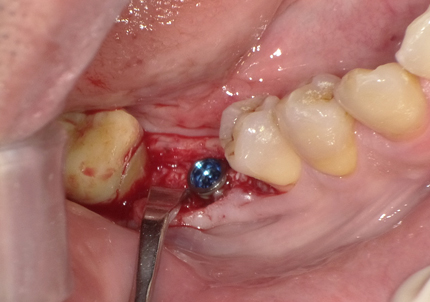

5.インプラント埋入(2021年6月)

※ 初期固定35N/cm確認する

6.二次手術

インプラント周囲の角化歯肉(付着歯肉:骨に固定されてる歯肉)の獲得を目的に歯肉弁を移動する